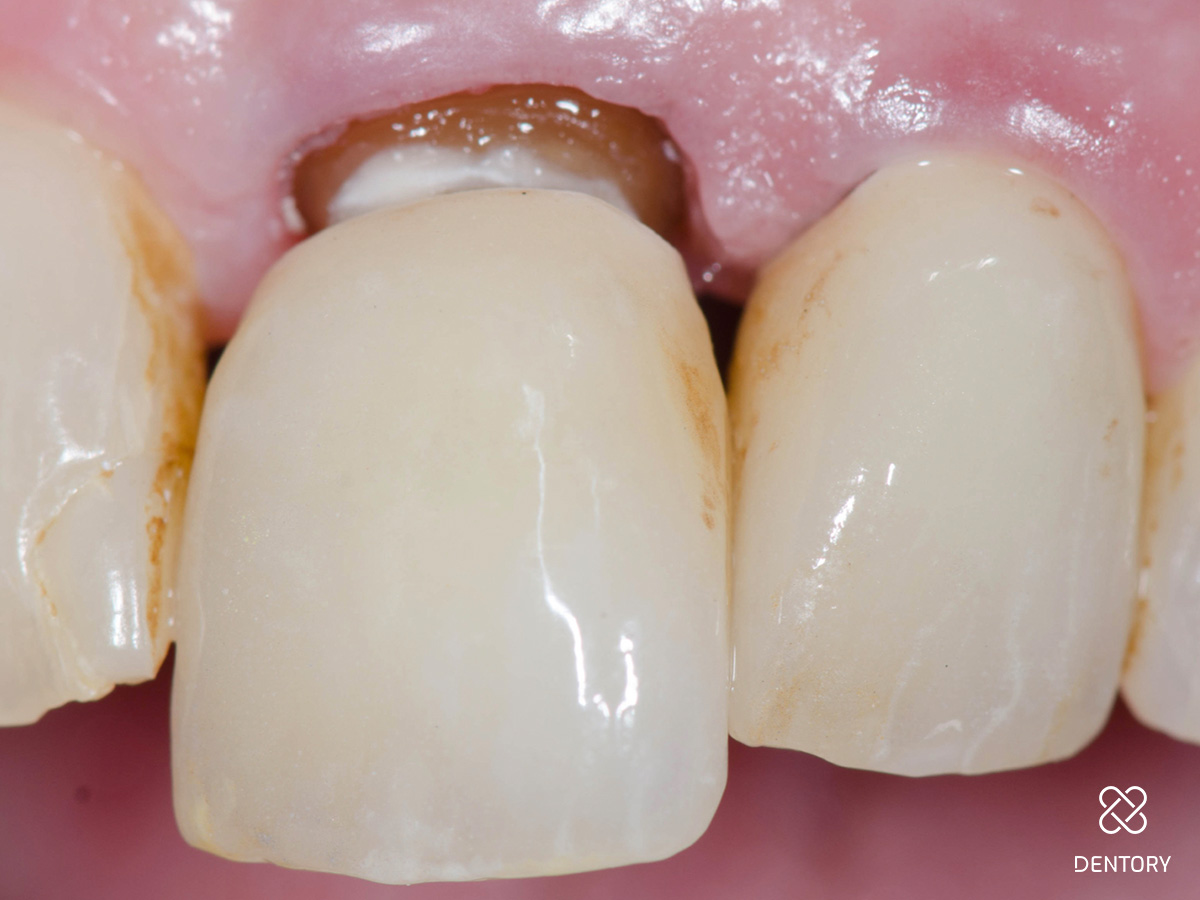

Abbildung 5

Einprobe an 22:Nach Abnahme der Provisorien werden die Stümpfe gereinigt und die Kronen einprobiert. Hier ist die Einprobe der Krone 22 zu sehen.